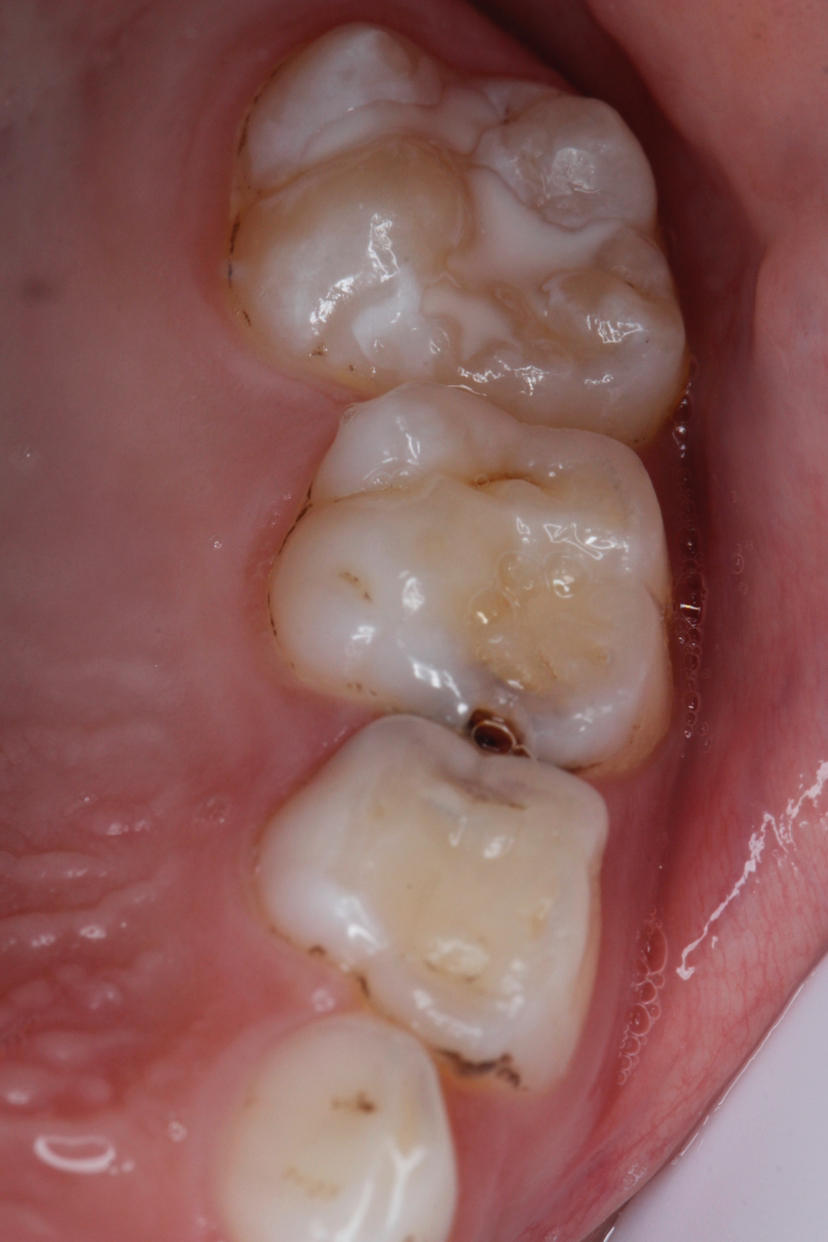

牙齿的咬合面布满了深浅不一的窝沟,这些细小的缝隙最容易藏匿食物残渣和细菌。儿童由于刷牙技巧不够熟练,很难彻底清洁这些部位。窝沟封闭技术就是将一种特殊的树脂材料涂布在牙齿表面,形成一层保护膜,将窝沟封闭起来,阻止细菌和食物残渣的侵入。

窝沟封闭的最佳时机是在恒磨牙萌出后尽快进行,一般在6-8岁和11-13岁这两个阶段。这时新长出的恒牙还没有受到细菌侵蚀,及时进行封闭能获得最佳效果。

即使进行了窝沟封闭,也要注意观察封闭剂是否脱落,定期复查。同时要坚持每天两次正确刷牙,使用含氟牙膏,这样才能全方位保护牙齿健康。